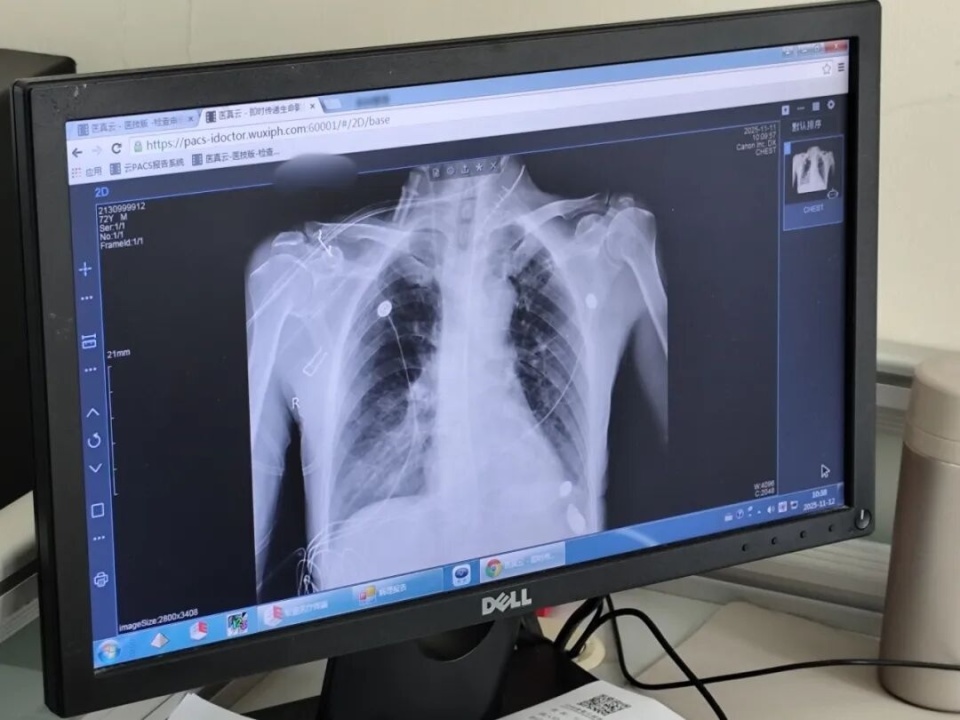

孙老伯患有反流性食管炎,近一个月感觉吞咽食物时有梗阻感,经检查确诊为早期食管癌。一般来说,手术是治疗食管癌的首选方式。但棘手的是,患者肺部曾有炎症,存在胸膜增厚、胸腔粘连,不适合进行传统的胸腔镜手术。该院胸外科团队经过评估讨论后,决定采用充气式纵隔镜联合腹腔镜食管癌根治术这一前沿微创术式。

“该手术无需开胸,仅通过颈部和腹部几个小孔进行操作,既避免了传统食管癌手术的大切口,也减少了术中单肺通气对患者肺功能的影响。尤其对于高龄或肺功能欠佳的患者,该术式能显著降低手术风险,减少术后并发症,加速术后康复。”无锡市人民医院胸外科主任医师、主任助理朱幸沨介绍,传统食管癌手术创伤大、恢复慢,而该微创术式极大地减轻了患者痛苦,也有效降低了肺栓塞、下肢静脉血栓等术后并发症的发生率。

朱幸沨介绍,充气式纵隔镜联合腹腔镜食管癌根治术通过颈部小切口进入,经过左颈部不到5cm的切口进入纵隔,手术空间狭小、操作困难,对医生技术的要求极高。“这一类手术在胸外科食管癌手术中属于‘顶尖手术’,不光要把食管游离出来,还要兼顾清扫周边的淋巴结,对主刀医生和助手来说都是一个很大的考验。”朱幸沨说。在团队密切配合下,手术顺利完成。术后孙老伯各项生命体征稳定,据了解一周左右就能康复出院。